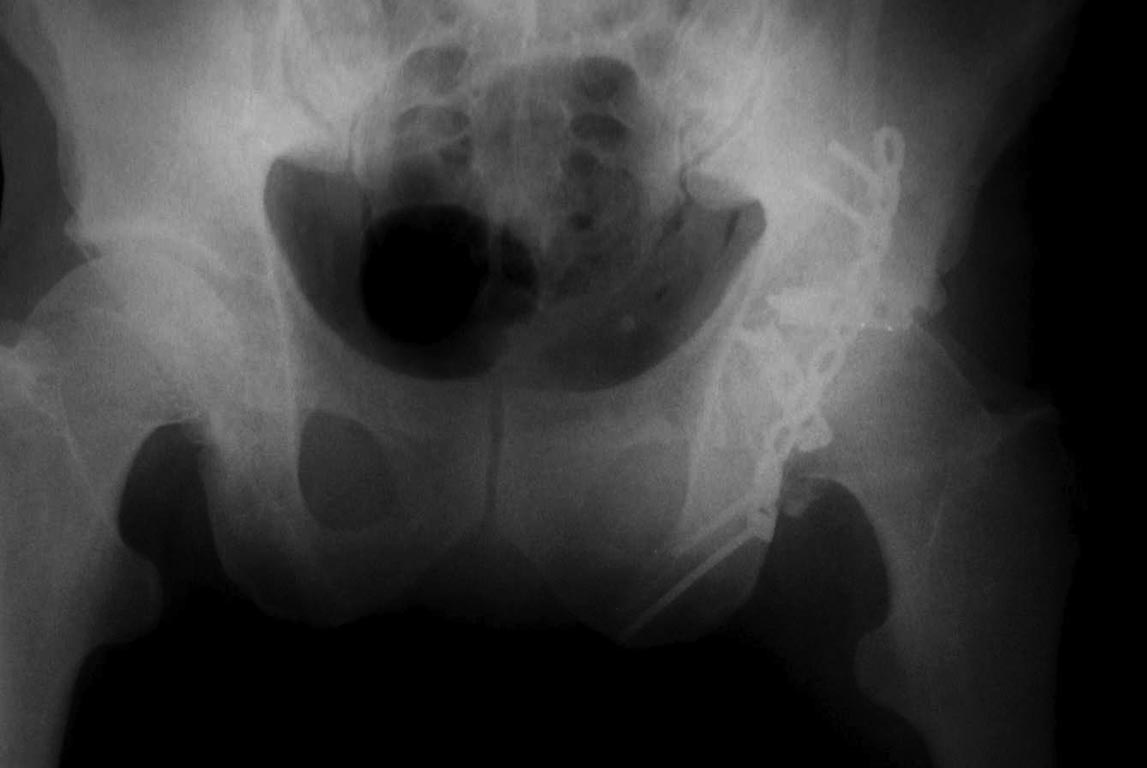

[Ortho] перелом проксимальной тибии + вывих бедра

сегодня только такое